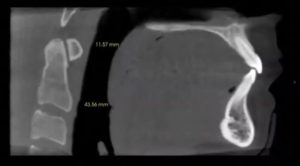

The CBCT measures an exact one-to-one ratio with no superimposed structures or magnification. This way, you can precisely measure in between implants to ensure you have the proper room from one implant to another, and you can assess the bone quality and quantity. Specialists can place a single implant in roughly 15 minutes if they are well prepared.